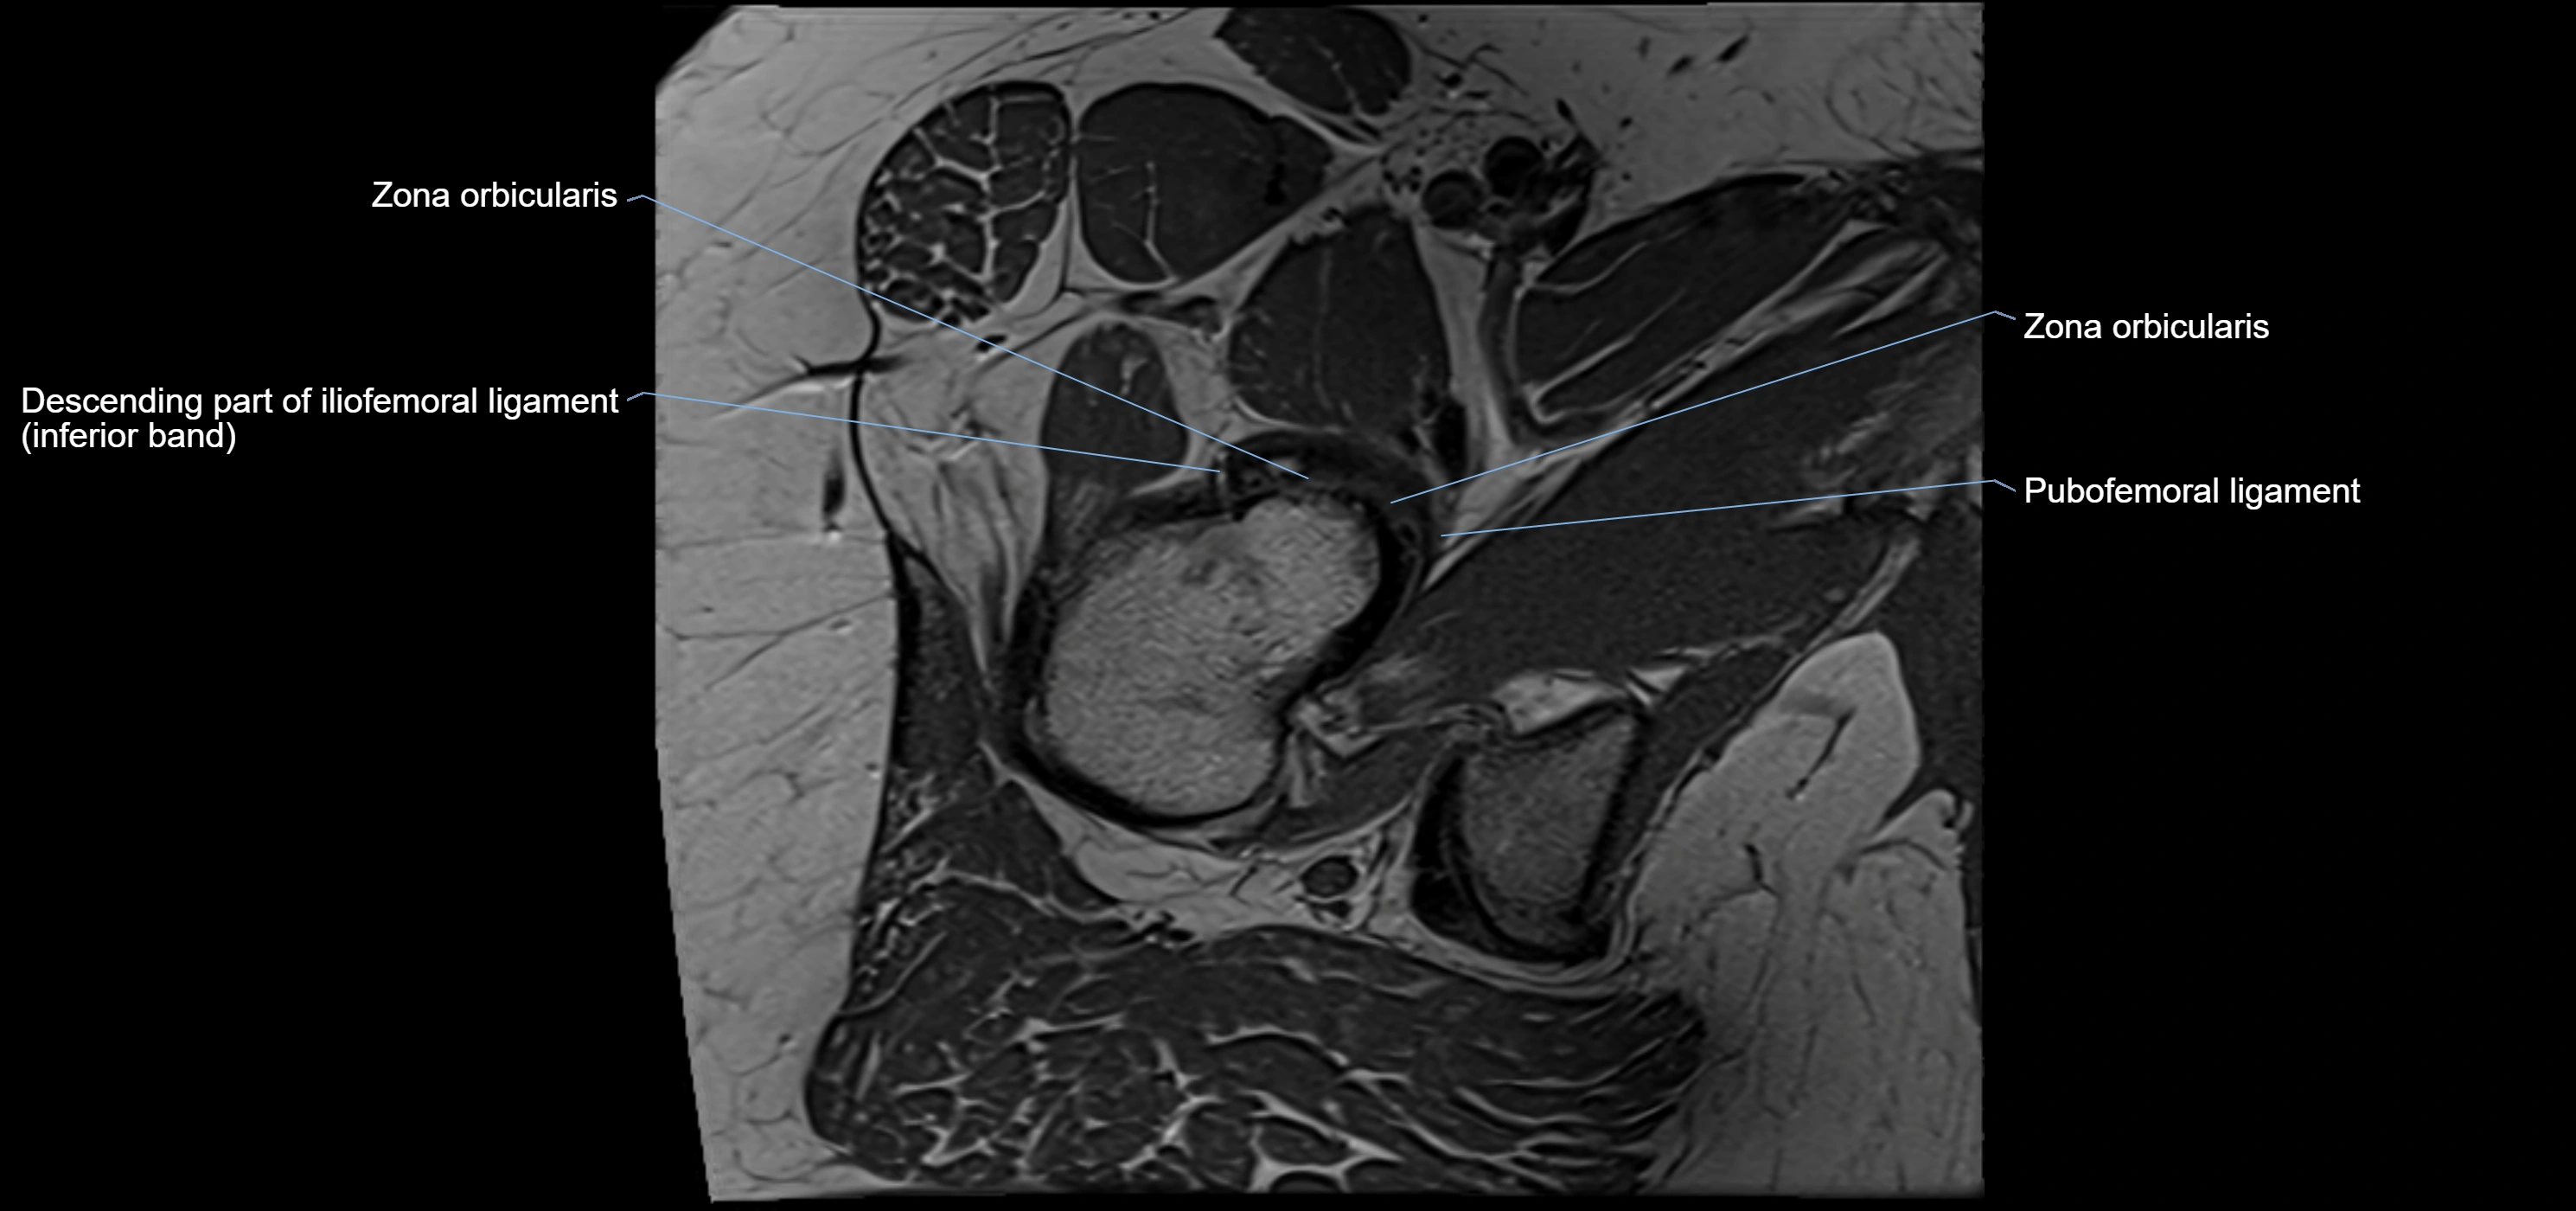

MRI Appearance

T2-weighted images:

• Labrum: low signal intensity (dark)

• Joint fluid: bright, making labral tears visible as fluid extending into or around labrum

MRI image

image